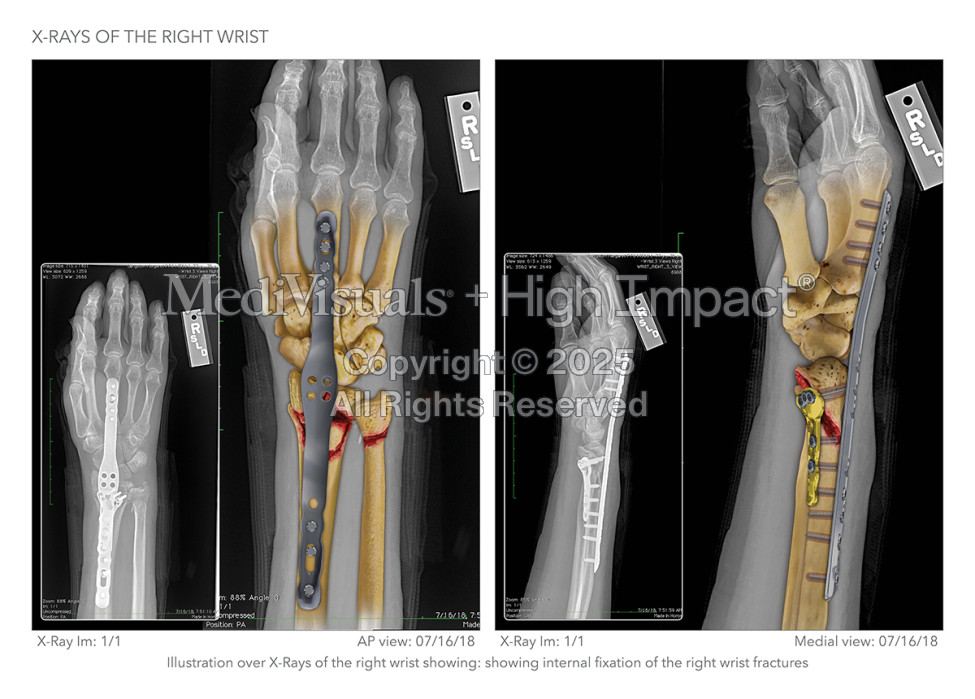

Mr. Sandefur needed the three Defendant contractors to understand the level of damage his client suffered as a result of their poorly conceived floor design that failed to comply with building standards. He tasked our medical illustration team with building an illustration series that would break down his client’s injuries, starting with the wrist.